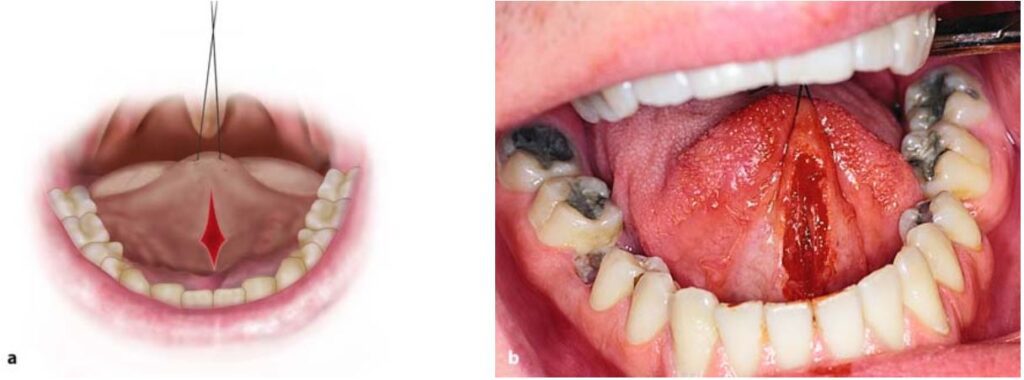

Thực hiện rạch theo kẹp cầm máu, đầu tiên là rạch ở phía trên, sau đó đến phía dưới kẹp (H10.84, 10.85).

Dùng kéo tỉa mô làm giảm căng mô xung quanh bờ tổn thương rồi khâu lại (H10.86 – 10.88).